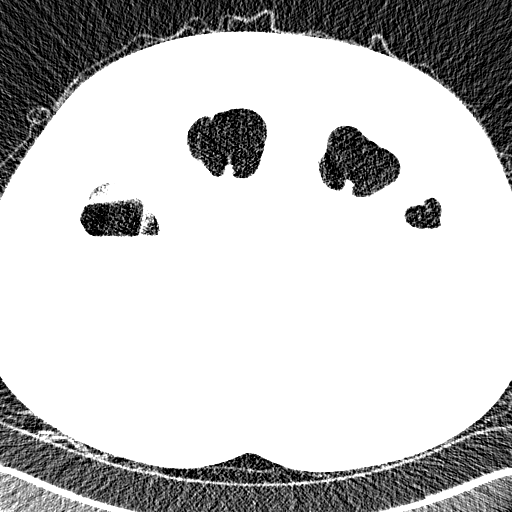

Elimination of noise in ultra low dose CT data

after smoothing